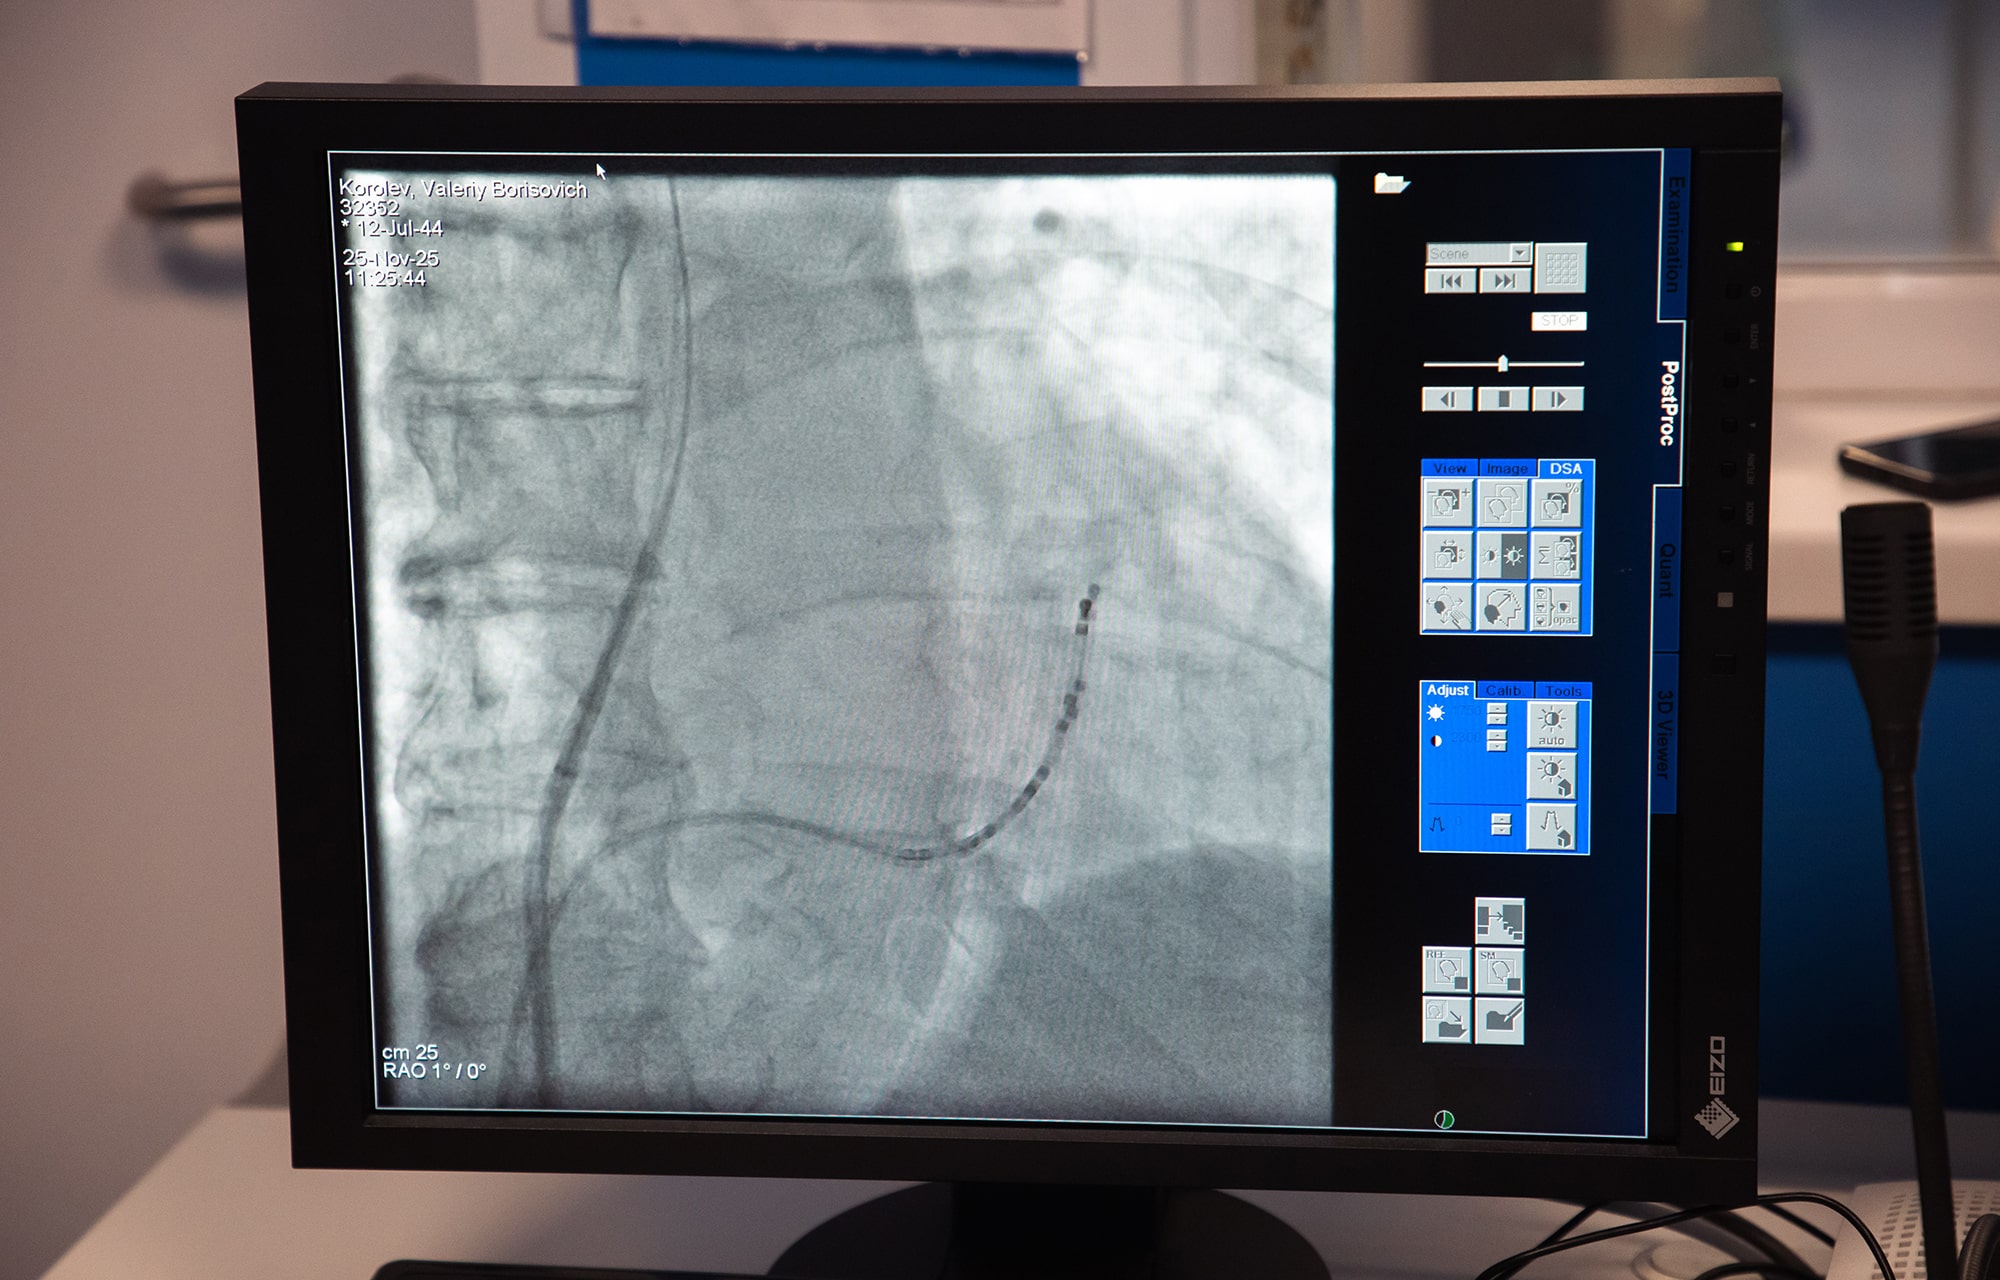

«Операция проводится эндоваскулярно, то есть без вскрытия грудной клетки. Используются ангиограф, навигация, современное криооборудование. Специалисты умеют делать операцию на уровне коллег из федеральных клиник», – рассказал главный врач ОКБ Сергей Козлов.

Преимущество метода криоаблации заключается в том, что он позволяет без осложнений и одномоментно уничтожить патологический очаг за счет воздействия низких температур. Общая продолжительность операции составляет от одного до полутора часов. Пациенты, как правило, сразу после операции чувствуют улучшение своего состояния и выписываются домой уже на 3-4 сутки под наблюдение кардиолога.